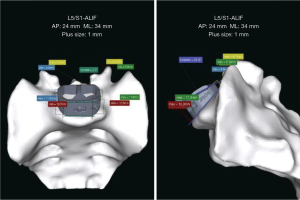

PS implants are meticulously engineered to conform to the individualized anatomical contours of each patient, addressing the complex geometric irregularities often present in pathological anatomy. This custom-tailored approach allows surgeons to design implants with precise dimensions and asymmetric sides as needed (12,16,18) (Figure 3). Custom design features include corrective angulation to restore lumbar lordosis, screw holes with preplanned trajectories that account for specific screw lengths, and end plate interface geometry matched to the patient’s unique anatomy (Figure 4). These enhancements ensure uniform loading across the end plates and implant, facilitating optimal integration with surrounding bone structures and significantly increasing the likelihood of achieving the desired preoperative alignment and biomechanical goals (23).

At the macroscopic level, the implant shape can be customized to perfectly match a patient’s unique anatomy, ensuring optimal fit and function within the intervertebral space. These “patient-specific” (PS) implants are tailored to the individual using anatomical data from imaging studies like computed tomography or magnetic resonance imaging scans (12) (Figure 2).